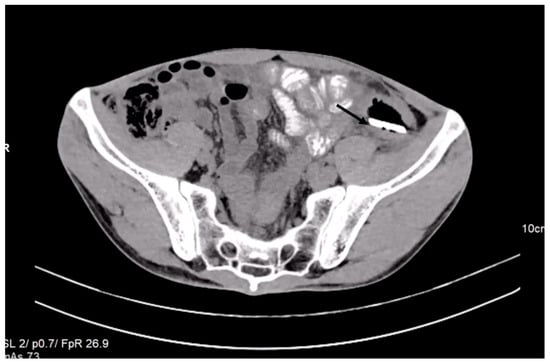

A CT scan performed before admittance showed, in the left iliac fossa, a foreign body with a density similar to the bone cortex, without reaching the specific density of the metal, and with an elongated shape similar to a knife blade tip (dimensions: 7.5 cm long at the base, 2 cm wide, and 4 mm thick). Most of this foreign body was located in the descending colon at the junction with the sigmoid. The tip of the foreign body was oriented craniocaudally and ventrally. It crossed the digestive wall and reached a transperitoneal position in the right abdominal muscle, on the left side, passing tangentially to the left lower epigastric vessels. In this region, the colonic wall appeared moderately thickened. There were small local intraperitoneal pericolic gas bubbles, no local fluid collections, no ascites, no pneumoperitoneum, and no signs of occlusion (Figure 2).

In such cases, a CT scan usually reveals a pneumoperitoneum’s presence. Our patient did not present pneumoperitoneum. A CT scan examination revealed local intraperitoneal pericolic gas bubbles and no pneumoperitoneum, which was evidence for chronic perforation.

This case is similar to the case presented here regarding the long period of retention in the colon and because of chronic perforation discovered at the moment of surgical laparotomy. In our case, the peculiarity was that the glass blade was lodged for 7 years in the sigmoid colon after a backstabbing of the patient. In the present case, chronic perforation was suspected based on the CT scan description of a foreign body with a sharp end penetrating the intestinal wall into the right abdominal muscle. CT scan imaging is able to predict with 82% to 90% accuracy if there is a large intestine perforation [32].

Moreover, the colonic wall appeared moderately thickened at the place of penetration. We were not certain what kind of foreign object was present in the sigmoid colon, because the X-ray and CT density of the object did not match the patient’s declarations, declaring he was stabbed with a knife blade. Generally, glass pieces appear on the radiography as radiopaque structures, being easy to visualize if the radiography is performed using the appropriate incidence [33]. Viewing a piece of glass on an X-ray depends on the size of the piece, but the density of the glass, regardless of size, is generally sufficient to differentiate a piece of glass from the surrounding tissues [34], as it was in our case.

Figure 2. Contrast-enhanced abdominal CT revealed the presence of a foreign object in the left iliac fossa.